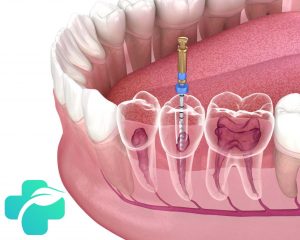

طی درمان ریشه، بافت عفونی یا ملتهب از داخل کانال ها خارج می گردد. این فرآیند می تواند منجر به تحریک بافت های اطراف و استخوان فک شود. لذا، درد بعد از عصب کشی یک واکنش فیزیولوژیک طبیعی به درمان محسوب می شود.

۱. کانال های ریشه فرعی یا پنهان

آناتومی دندان پیچیده است و گاهی کانال های ریشه فرعی شناسایی نمی شوند. باکتری های باقی مانده در این کانال ها باعث عفونت و درد دائمی بعد از عصب کشی می شوند.

برای تشخیص این کانال ها، ممکن است نیاز به میکروسکوپ دندانپزشکی یا عکس برداری سی بی سی تی باشد. درمان مجدد ریشه (ری روت تراپی) برای پاکسازی آن ها ضروری است.